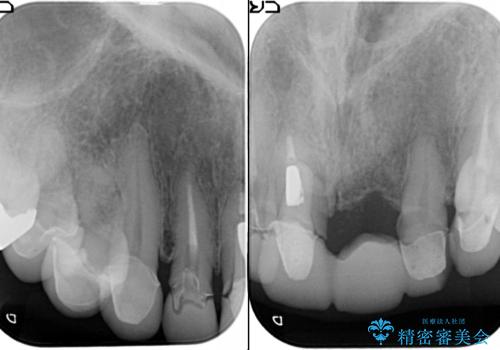

[ セラミック治療 ] 歯ぐきの際の黒ずみを改善したい

- 歯ぐきとセラミックの間の黒ずみが目立つので、きれいに治してほしい。と希望され来院されました。

歯ぐきの位置が変化しクラウン下の歯が見えるようになってしまったことで、審美障害が生じている状態です。

クラウンマージンの再設定を行うことで、黒ずんだ部分を再度覆い、審美障害を改善します。